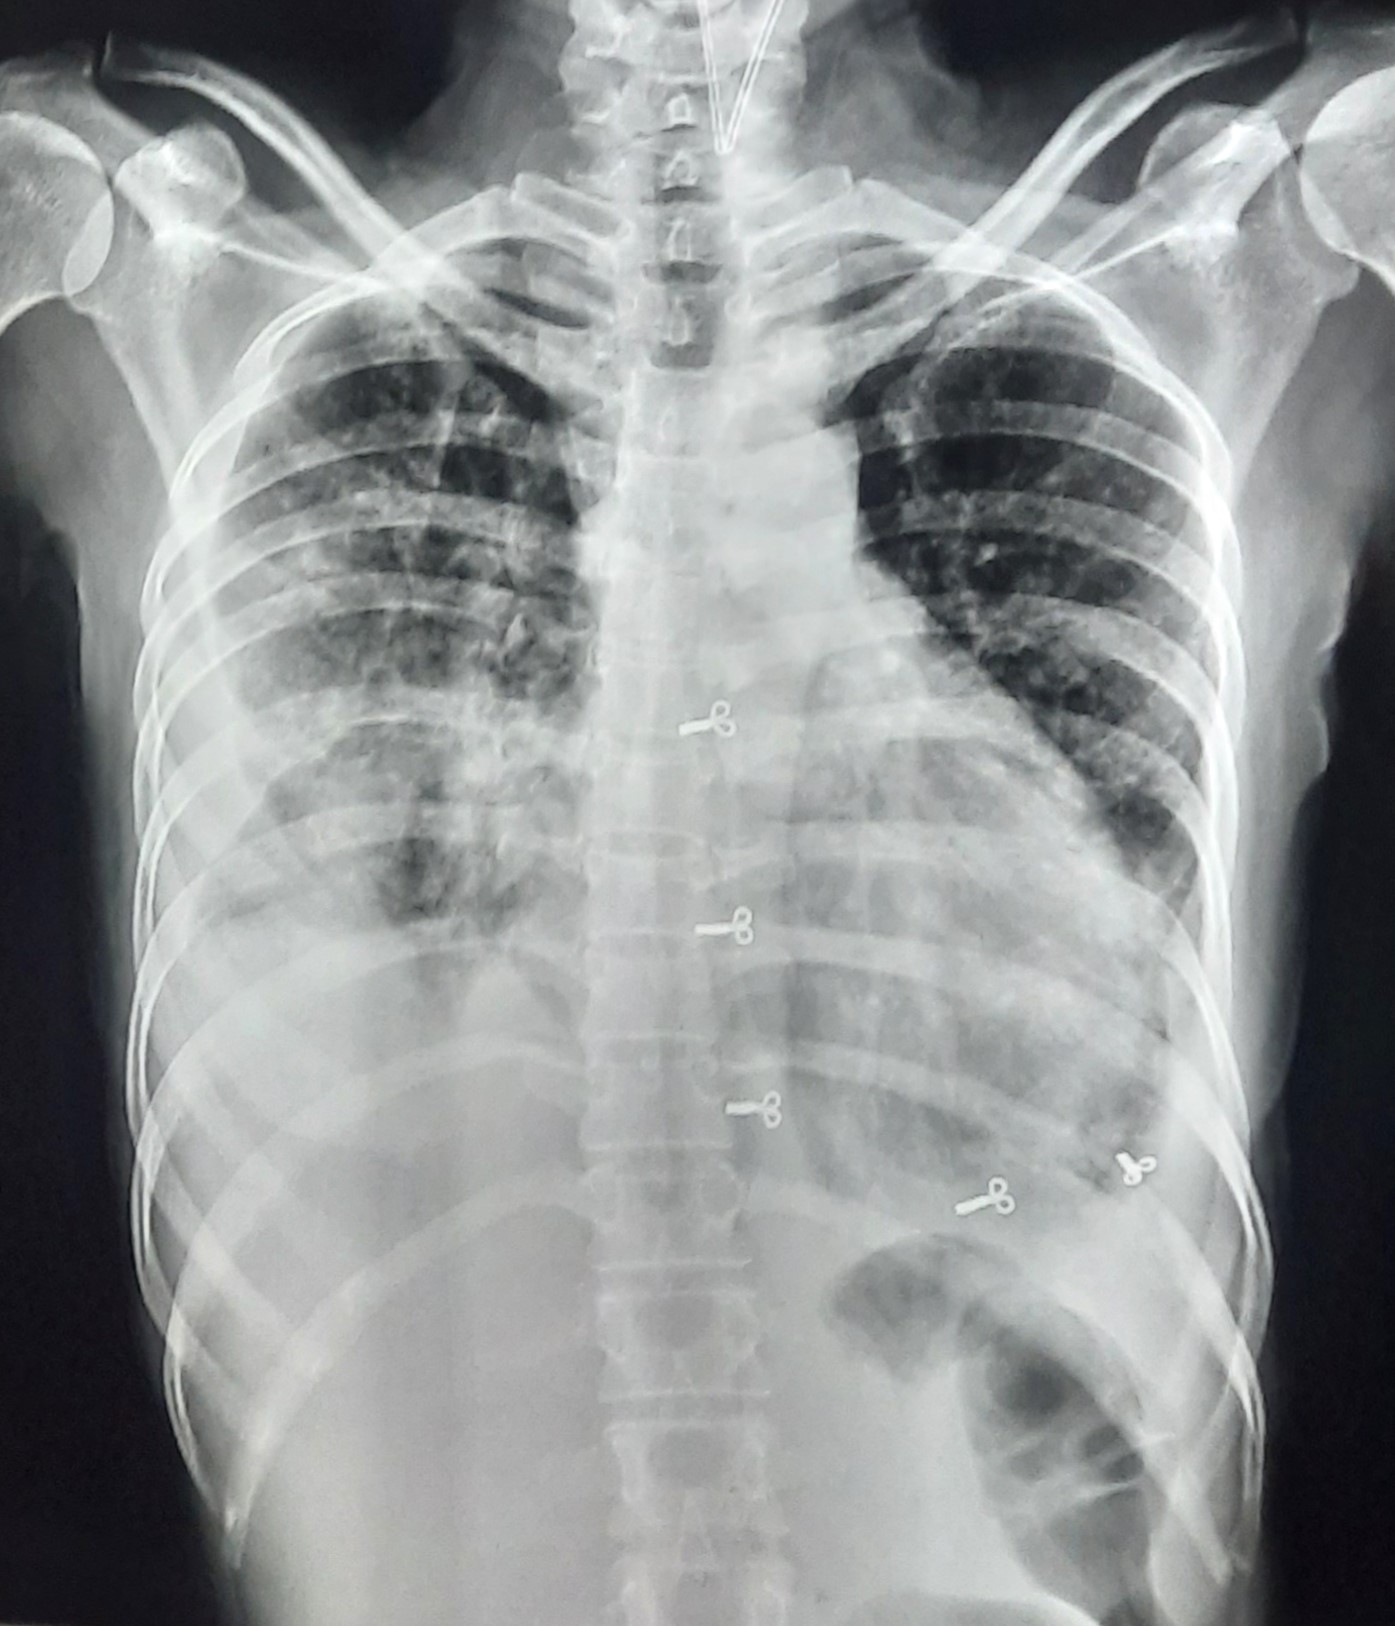

| 52 | IGGMC, Nagpur, Nagpur | P2 | 29-4420 | Hamida Bano | Consent taken on Paper | 56 Yrs. |

Provisional Diag : Post TB Sequelae With Reactivation?

Final Diag : Post TB Sequelae |

Post TB Sequelae | Tracheal Pull Left Side, Left Mid Zone & Upper Zone Fibro cavitary Lesion Present, Compensatory Right lung Hyper Infiltration Present, Few ill-defined Bilateral Lung Opacity Presnt | Abnormality visible on x-ray |